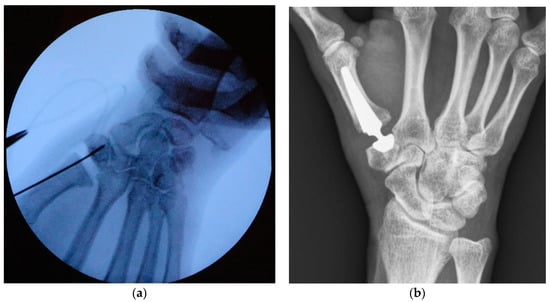

2.1. Surgical Technique

2.2. Clinical and Radiographical Evaluation